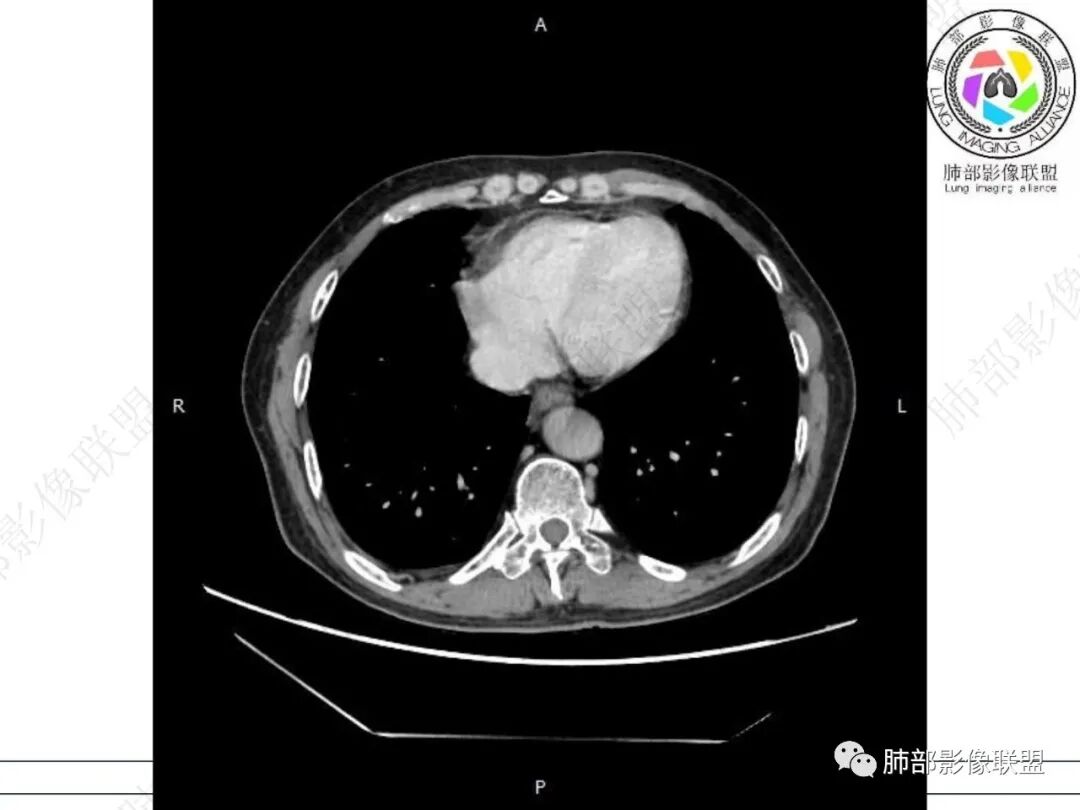

气管隆突下团片影,其内积气,与食道分界不清,食道壁增厚,管腔狭窄,右下肺实变影,支气管壁增厚,考虑食管支气管瘘并右下肺感染,食道肿瘤病变不除外

支持食管支气管瘘(考虑食管癌)伴后纵隔及右肺感染,食管管壁明显增厚,管腔狭窄,相邻右侧后纵隔内软组织内可见气体影,与食管分界不清,右肺有实变及不张。

右肺下叶背段条片状实变影,内可见支气管走行,支气管有狭窄有扩张,周围可见磨玻璃影,隆突下团片影,内密度不均可见气体影,与周围结构界限不清。食管下段壁增厚,管腔狭窄,右肺下叶慢性炎、肺不张,考虑食道肿瘤所致气管食管瘘。

右肺下叶沿肺叶肺段分布斑片、条片状影,以下叶背段为显,边缘模糊,内可见支气管走行,局部支气管管壁增厚,右侧胸腔少量积液。纵隔隆突下可见不均匀软组织密度影,与周围结构分界不清,内见气体密度影,与食管及相邻右肺支气管之间未显示通道。邻近食管下段壁明显不规则增厚,增强后食管管壁明显不均匀强化,可见线样强化的连续完整粘膜影。